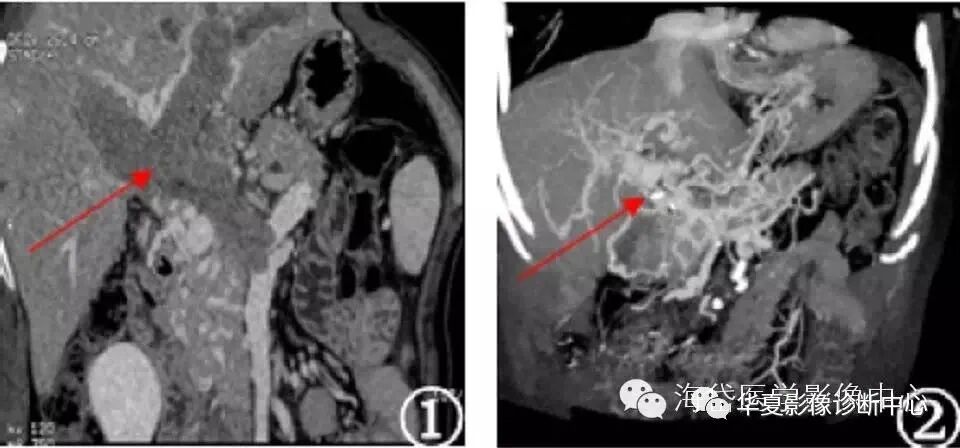

图5 门静脉主干狭窄闭塞伴侧枝循环

图6 门静脉主干狭窄闭塞伴侧枝循环,脾肾静脉交通胆囊静脉增粗形成假肿瘤征